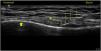

Persistent knee pain in patients around the fifth decade of life is a frequent cause of attention in rehabilitation consultations. The most common cause of diagnosis is knee osteoarthritis, considering the existence of different degrees seen in simple radiographies. The advanced degrees present joint space reduction, osteophytosis and subchondral sclerosis; however, in the initial degrees, the findings are more subtle and sometimes nonexistent for conventional radiology. Clinical ultrasound has partly come to fill this «diagnostic gap», making it possible to detect meniscal extrusions and small osteophytes as signs of incipient osteoarthritis and to relate them as triggers of pain. In clinical practice we find a group of patients who, with little or no radiological alterations, present persistent and severe pain with medial predominance in most cases. These, until the appearance of the current evidence, were subsidiaries of meniscectomies. At this moment, when meniscectomies are not recommended, it is necessary to find a treatment for those cases in which conservative and non-ablative interventional treatment has failed. In this context, the possibility of using radiofrequency arises. Its use is widespread in the case of tricompartmental and advanced osteoarthritis. However, little data is available on its usefulness in cases of medial meniscal extrusion. It seems that thermal radiofrequency has greater effects than pulsed radiofrequency. We present a clinical case where thermal radiofrequency of the medial genicular nerves of the knee is proposed as a therapeutic alternative for chronic pain secondary to medial meniscal extrusion associated with incipient knee osteoarthritis, with the result of a decrease in pain (VAS 8 before treatment, VAS 1 after one year), subjective improvement of 80% and gait capacity.